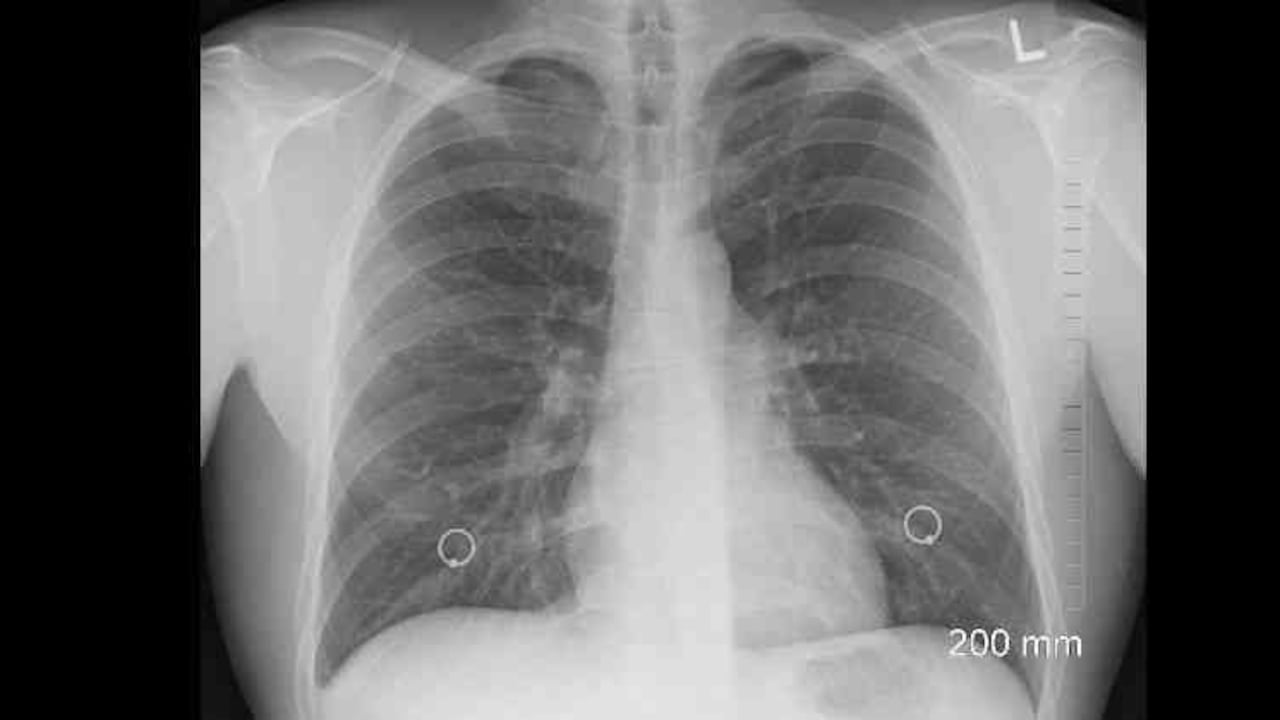

La FPI provoca un proceso de cicatrización en el pulmón que va dejando poco a poco al órgano incapacitado para hacer su función. Hace cinco años, no había mucho para ofrecerles a estos pacientes fuera de oxígeno, terapias de rehabilitación y paliativos para los síntomas. El 20 por ciento de los diagnosticados terminaban en lista de espera para trasplante de pulmón pero esta solución no era la panacea. Fue así como Nathan se familiarizó con esta enfermedad. Ese interés lo llevó a involucrase en investigaciones clínicas para probar que una molécula, pirfenidona, podía contrarrestar la enfermedad. Luego de muchas investigaciones en las que se demostró que detenía el progreso de este mal, la droga fue aprobada en octubre del 2014 por la FDA y recientemente por el Invima en Colombia. Este hecho ha marcado un hito en el manejo de la enfermedad y hoy es crucial detectarla a tiempo “pues así se logra preservar el pulmón desde el principio y no tarde cuando ya se ha perdido mucha de su función”, explica.